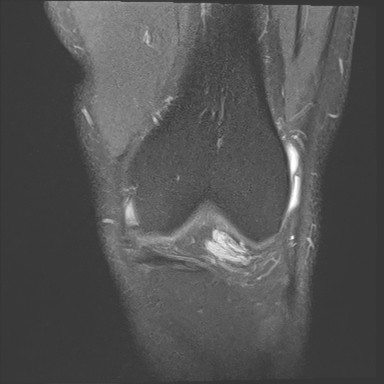

Figure 2 for case Orthovisc injections

Figure 2